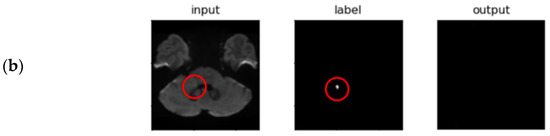

- Indirect Volume Estimation (Using 2D Segmentation)

3.2. Segmentation Performance